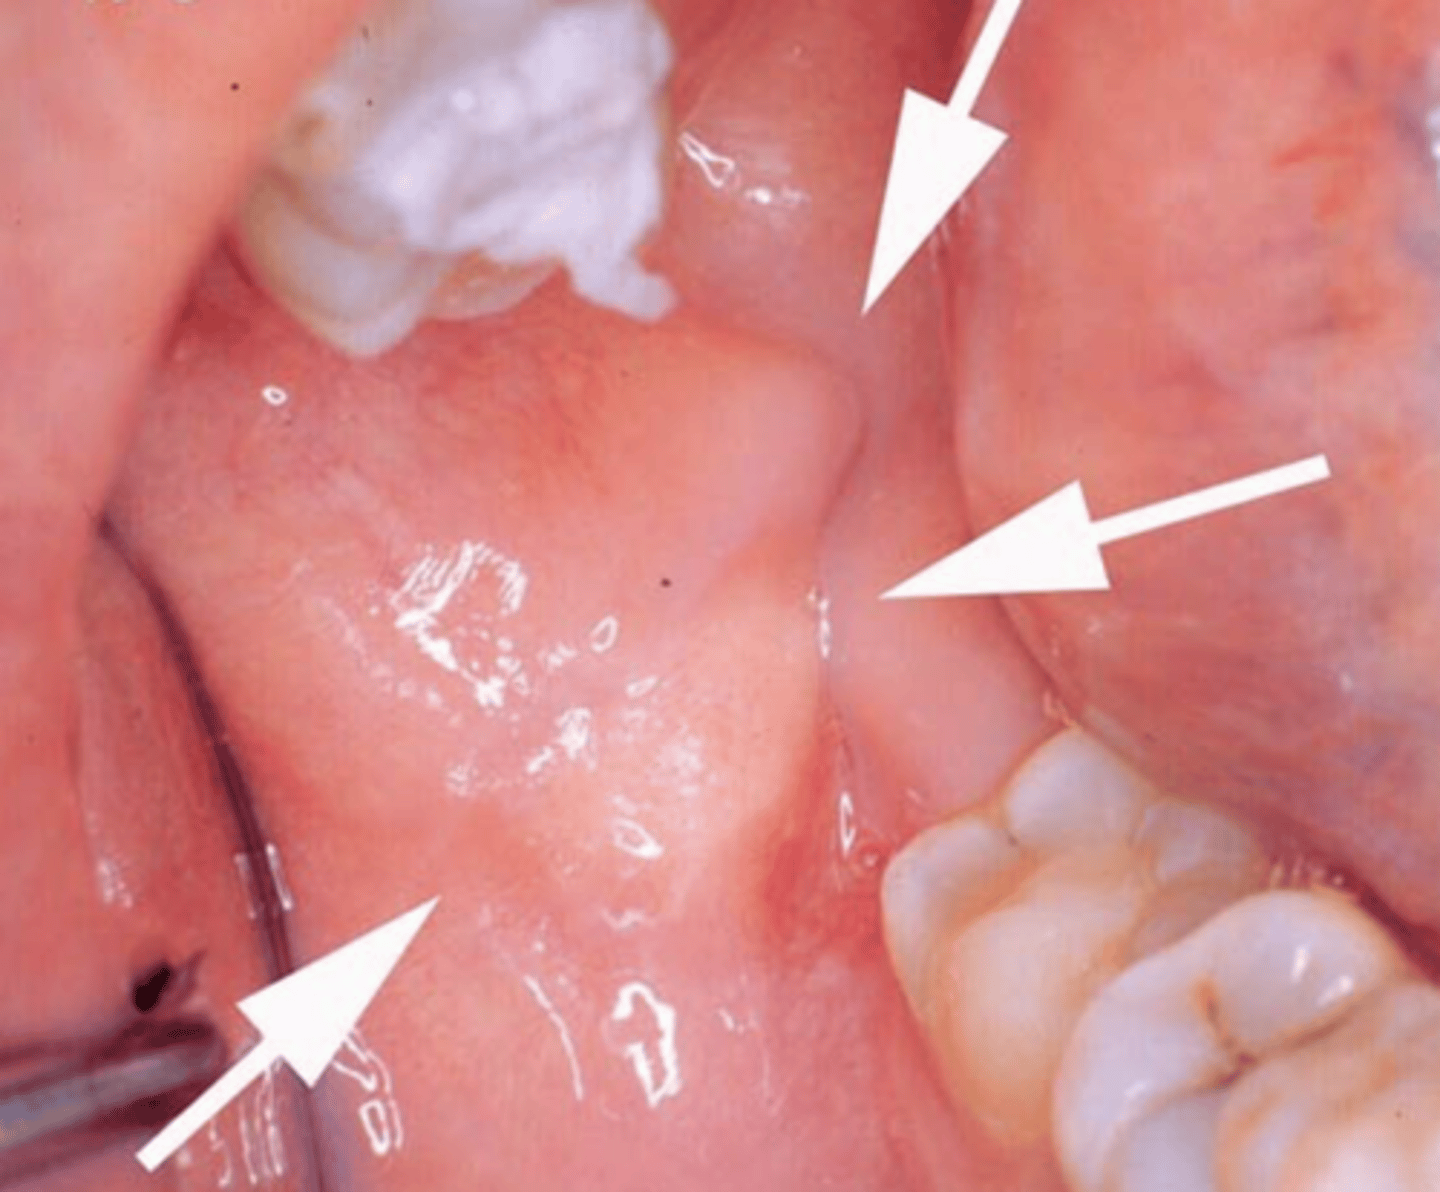

describe how a granular cell tumor would look/feel clinically:

yellowish, raised, firm to palpation, non-ulcerated lesion

this is painless

where is the most common site in the oral cavity for a granular cell tumor?

tongue